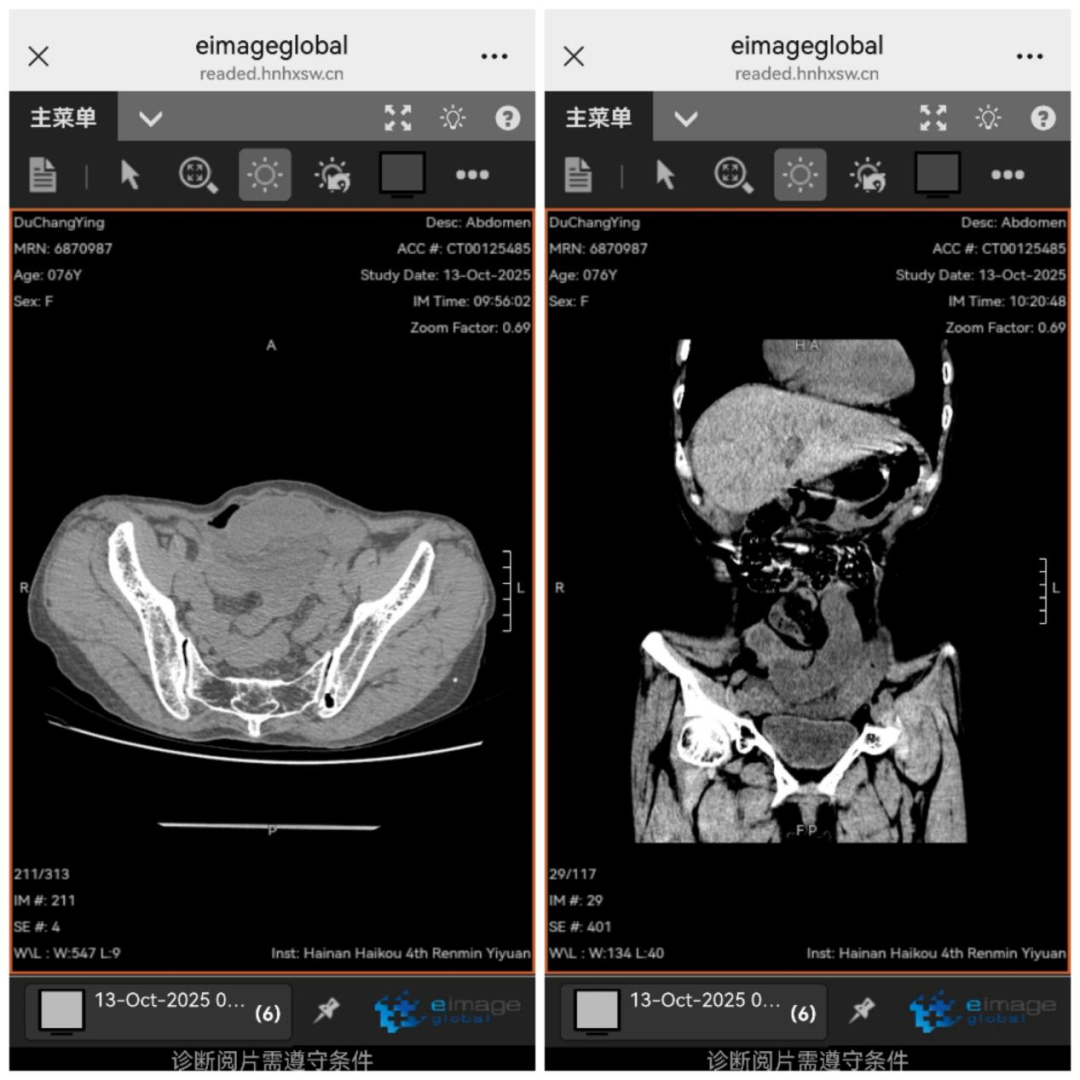

家人立即将杜奶奶送至我院急诊科。入院时,她生命体征极不稳定,收缩压超190mmHg,心率仅45次/分,仍间歇性剧烈腹痛。急诊科林亚发主任迅速指导救治,并紧急邀请普通外科会诊。经腹部CT及双次心电图、心肌酶检查,排除急性心梗、腹主动脉夹层后,将杜奶奶收治至普通外科。

入科后,普通外科刘琪主任仔细检查,发现患者突发剧烈腹痛、腹肌软、中下腹部压痛、无明显腹胀,起病时间短,无典型肠梗阻症状。与放射科共同阅片后,考虑小肠肠管水肿,刘琪主任判断闭袢性小肠梗阻可能性极大,同时稳定患者生命体征,立即安排腹部增强CT检查。

检查显示,患者腹部积液快速增多,肠管扩张增厚。刘琪主任指出病情急剧恶化,疼痛可能引发疼痛性休克,体液快速丢失会导致失血性休克,肠道坏死细菌外移,坏死组织释放的炎性介质会冲击多脏器功能。时间紧迫,必须立即手术探查。随后,麻醉科蔡弥松主任、重症医学科吴清松主任应邀协诊,共同制定围手术期治疗方案。在患者家属充分信任下,手术迅速展开。